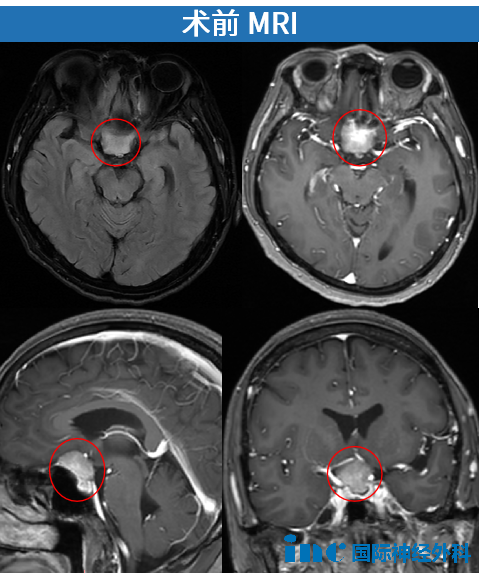

2024年12月17日,身处国外的陈女士因面瘫和视物模糊症状,确诊为鞍区脑膜瘤。病情进展迅速,短短4天后,她紧急返回国内。详细检查显示肿瘤位于鞍底区域,尺寸约2.6cm×2.5cm。

时间持续流逝,视觉功能逐步丧失。儿子在安抚恐惧母亲的同时,积极奔走求医。2025年1月3日,他们获得巴教授关键评估意见:"手术非常紧急!"此时陈女士双眼视力呈进行性下降,检查结果显示双眼视力0.2(正常值1.0),双眼视野存在严重缺损。

由于肿瘤位于前颅底区域,生长于双侧视神经之间,随体积增大逐渐压迫视神经结构。此外,肿瘤位置险要,已波及垂体及垂体柄区域。

这不仅涉及肿瘤本身问题,肿瘤还会压迫供应视神经和视交叉的血管系统,损害视神经血液供应,极易引发肿瘤和视神经梗塞,导致患者完全失明。